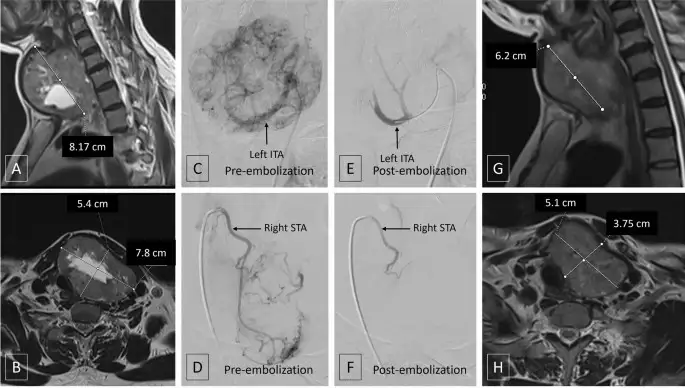

Following embolization, the body begins a gradual healing response. Over time, the treated tissue may reduce in size and the sense of neck pressure or compression can improve. If the treated portion was contributing to overactivity, symptoms may improve as function in that segment reduces. Because the effect develops gradually, improvements are typically measured over weeks to months, often with follow-up imaging and thyroid function testing.

Does Thyroid Artery Embolization Really Work?

The thyroid artery embolization is an option for some people but it does not work the same for everyone. The kind of thyroid problem you have the size of the thyroid tissue and how many blood vessels are in it all play a role in how it works. The number of nodules what they are like your thyroid hormone levels and which blood vessels are used are all factors. This is why doctors need to choose the patients, for thyroid artery embolization and use the right technique to block the blood vessels. The thyroid artery embolization is a procedure that depends on things, including the thyroid condition so it is crucial to get it right.

For patients with symptoms the main goal is to reduce the pressure sensation make swallowing more comfortable and decrease the visible neck swelling over time. This improvement usually happens slowly. Doctors can use ultrasound or other imaging tests to track the progress of the thyroid symptoms depending on the treatment plan. If the thyroid hormone activity is a problem the doctor will do hormone tests as part of the follow-up to make sure the thyroid hormone activity stays within a range for the patient, with compressive symptoms.

A realistic expectation is that symptom improvement may develop over weeks to months rather than overnight. Your doctor will explain what level of improvement is possible based on your specific diagnosis.